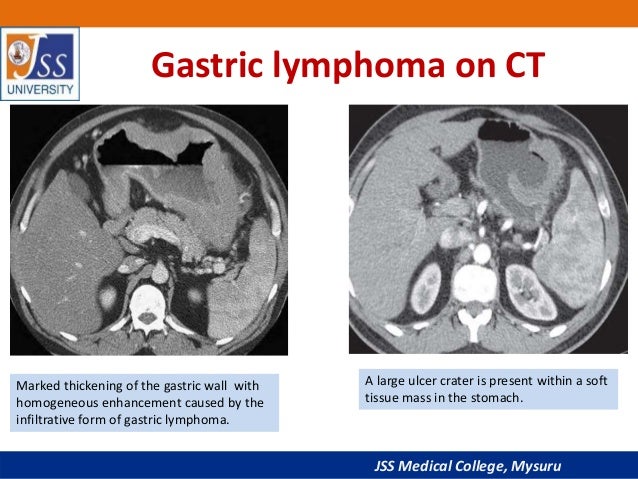

Thick tortuous folds or lobulated filling defects in the cardia or fundus. Right gastroepiploic artery inferiorly and left gastroepiploic artery and short gastric arteries superiorly fundus of the stomach. Results of surgical treatment of carcinoma of the esophagus and gastric cardia. The collection of cases presented here comprises only that material which is rare in our experience or quite new to us.

A healthier weight from surgery can help improve or resolve many obesity related conditions such as type 2 diabetes high blood pressure joint pain heart disease and more. Medically treated small gastric ulcer. Left and right gastric veins drain to portal vein. Ugis has a 70 90 detection rate.